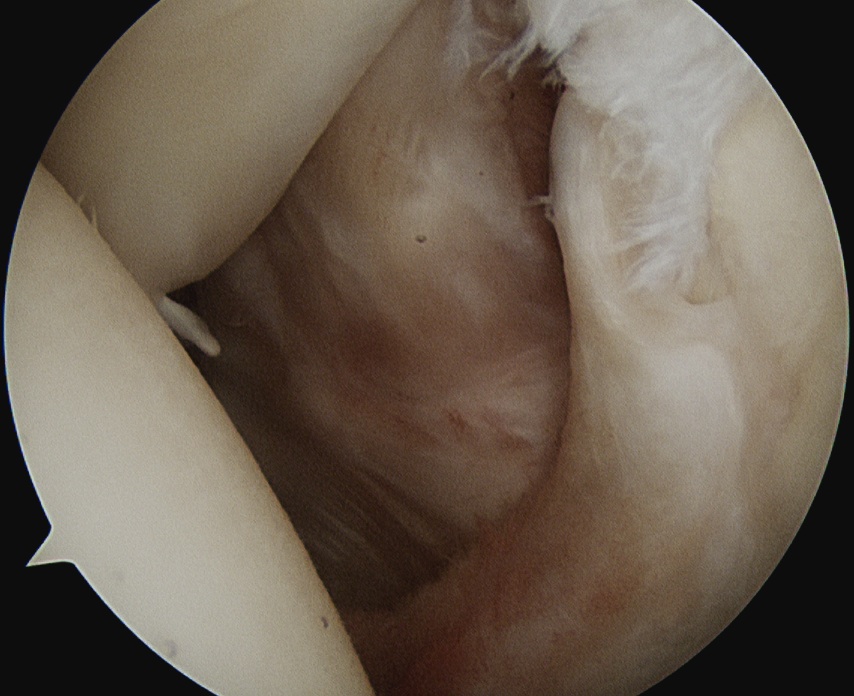

Lateral traction sutures placed in subscapularis, then cautery used to remove scar tissue and recreate rotator interval